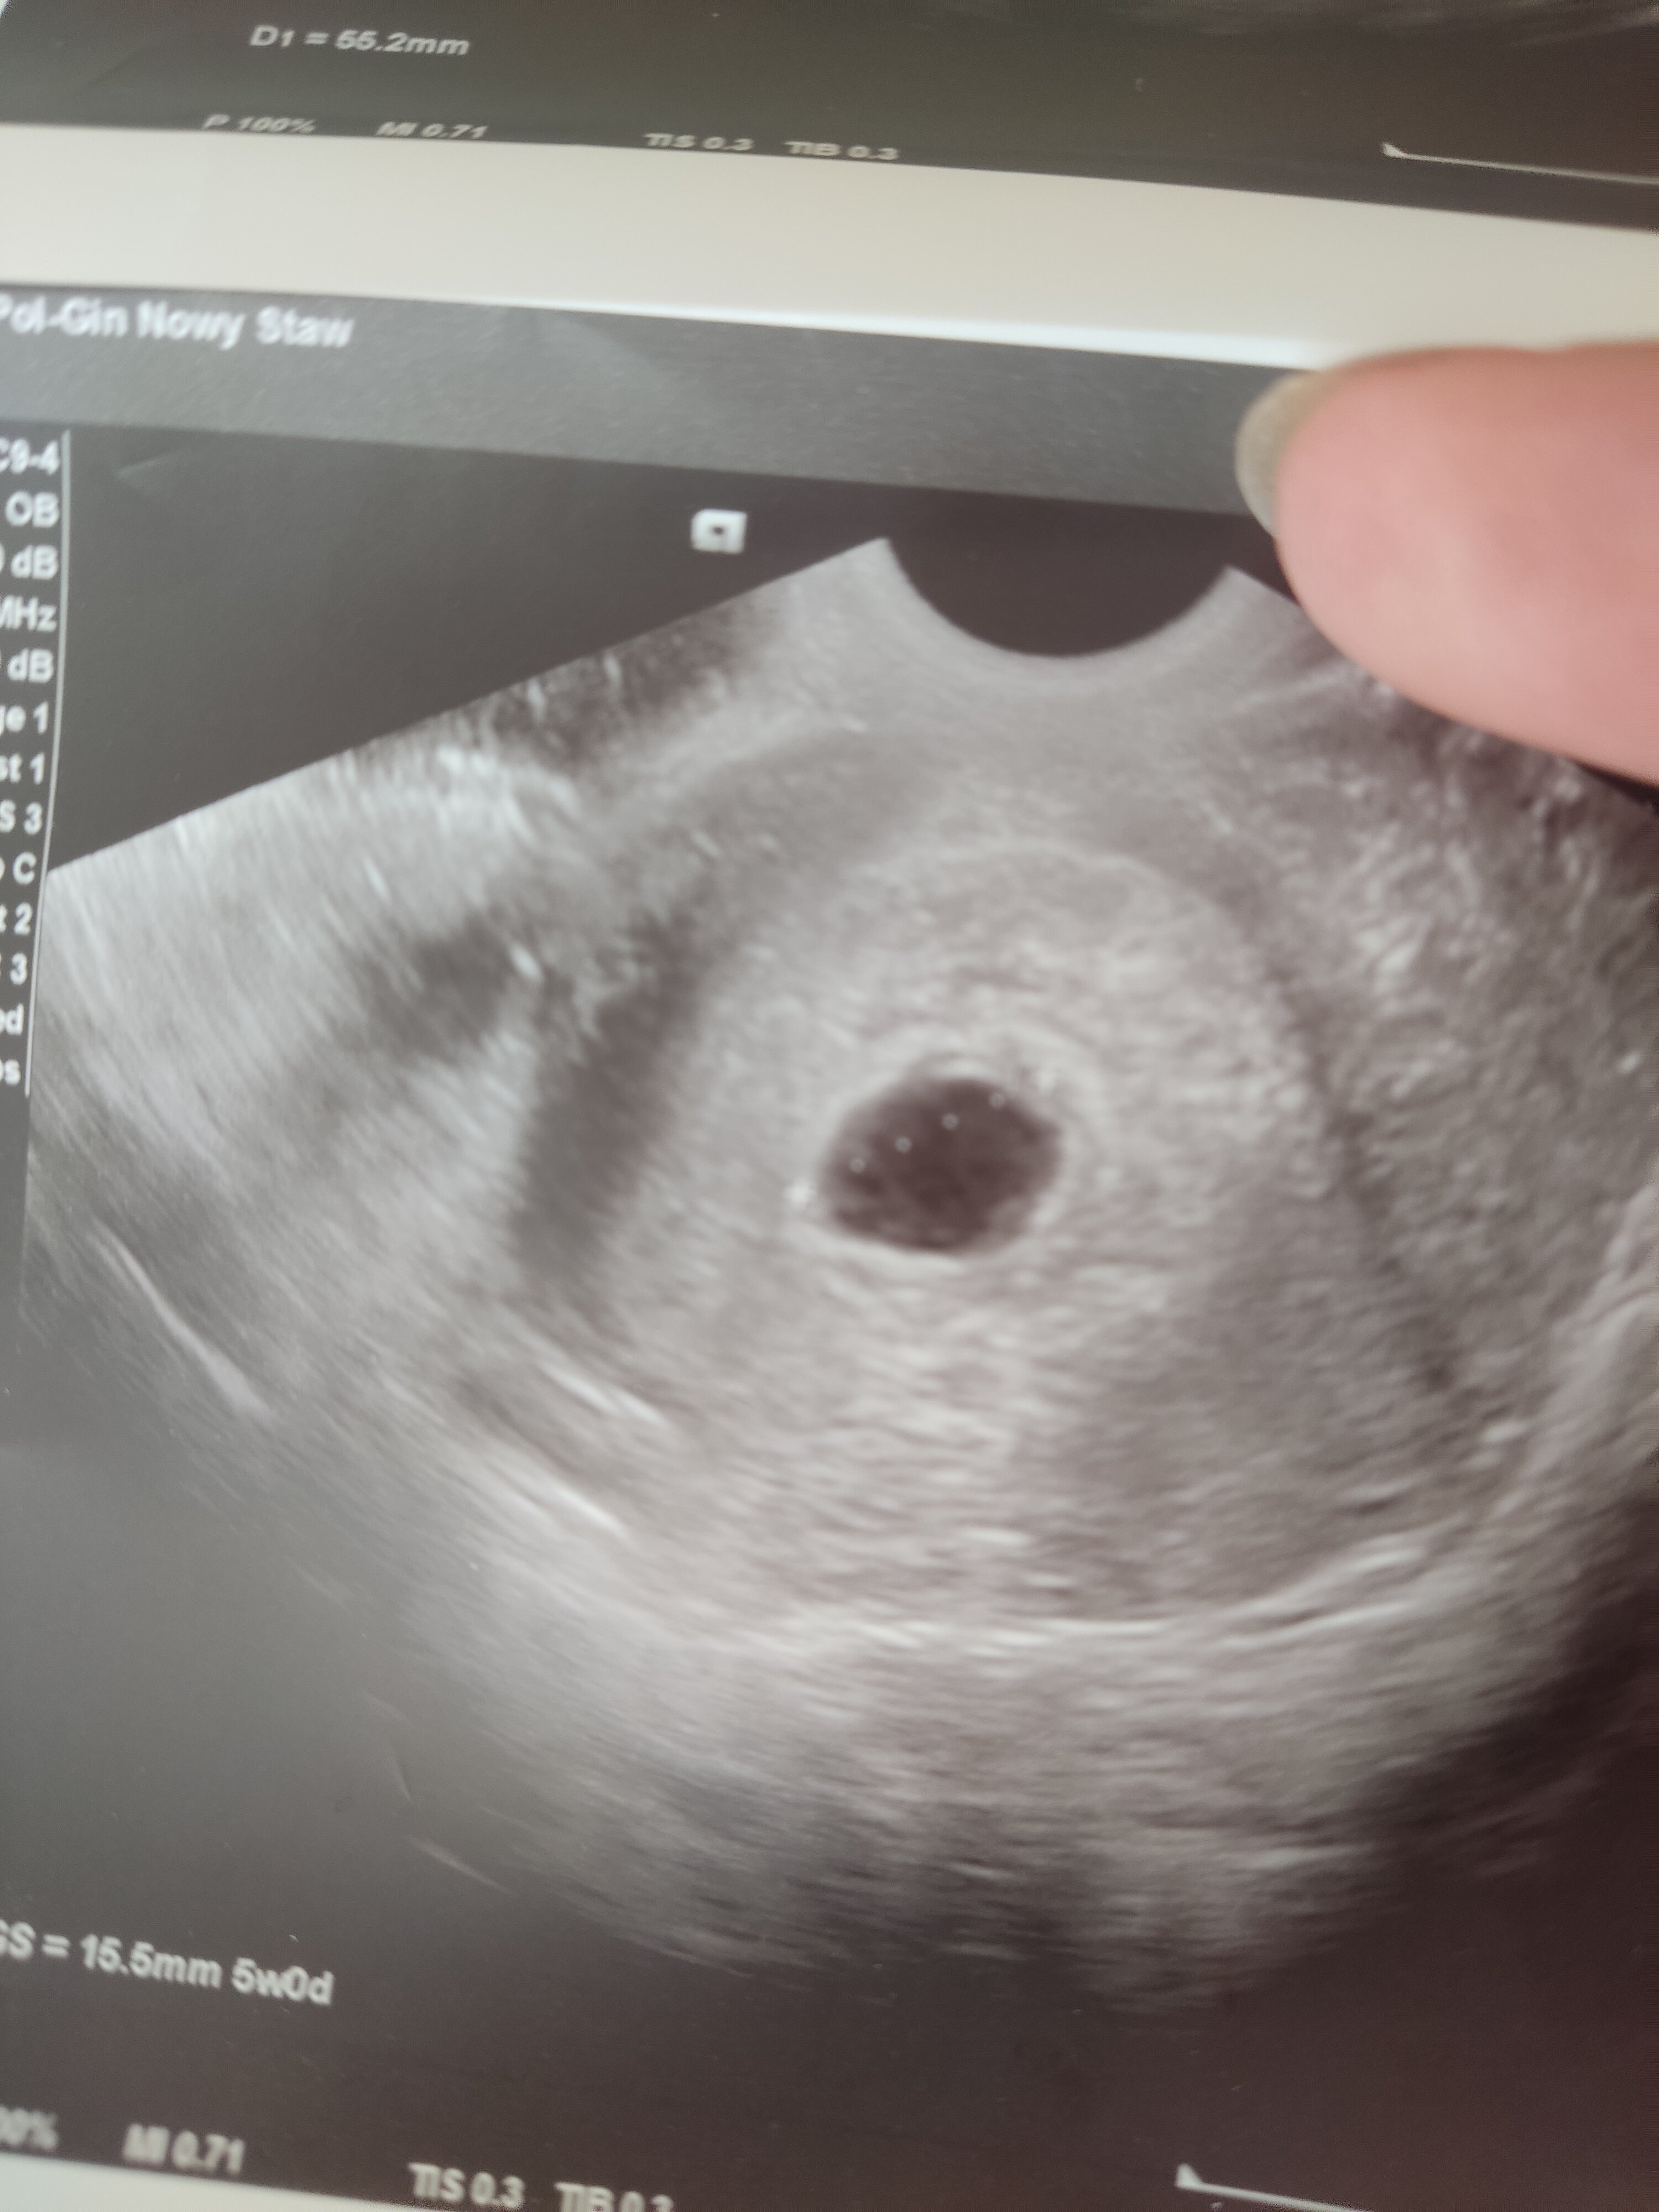

Dzisiaj pierwsze badanie u ginekologa, z ostatniej miesiączki wychodzi 7+5 natomiast z usg młodsza. Pęcherzyk jest wielkości 15,5mm co wdg internetu wskazuję na 6-7 tydzień ale ginekolog stwierdził że to 5tc+0 i mam przyjść za tydzień. Powiedział "spodziewałam się dużo starszej bo dacie ostatniej miesiączki ale przyjdź za tydzień, powinno być serce jeśli się rozwija". Straciłam nadzieję, bo okres miałam 8 kwietnia a 4 maja test wyszedł mi pozytywny, gdyby ciąża była tak młoda jak on mówi to raczej niemożliwe żeby wtedy już była druga kreska na teście. Raczej obstawiam że ciąża się nie rozwija chociaż od tygodnia moje objawy się nasilają. Co myślicie? Widzicie coś na tych zdjęciach? Niestety opisu nie dostałam, bety chyba nie ma sensu robić bo nie robiłam jej ani razu więc chyba lepiej czekać na usg za tydzień :/

Pęcherzyk wygląda na pusty no, ale to tylko zdjęcie nie wiem czy lekarz widział pęcherzyk żółtkowy. Tak czy tak trzeba sprawdzić za kilka dni, nic innego się tu nie wymyśli